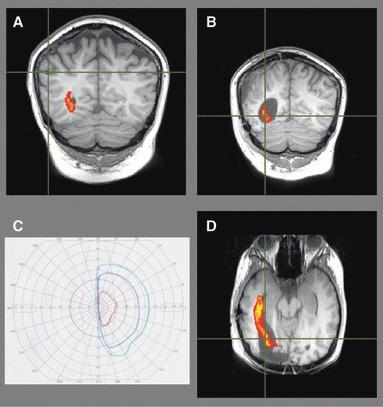

About one-third of patients with epilepsy are refractory to medical treatment and may be amenable to surgery. However, in patients with lesions on or near the presumed course of the optic radiation, the potential benefits of resection must be balanced against the risk of a visual field deficit. This study demonstrates the utility of diffusion tensor imaging (DTI) tractography in delineating the course of the optic radiation and its relationship to the epileptogenic lesion prior to epilepsy surgery.

Anatomic and DTI scans were acquired on 10 patients with medically refractory epilepsy undergoing presurgical evaluation at the National Hospital for Neurology and Neurosurgery. Five patients underwent surgery and repeat scans postoperatively. The optic radiation was delineated and visualized in relation to the lesions on anatomic images and in three-dimensional (3D) reconstructions. Preoperative and postoperative visual fields were acquired by Goldmann perimetry.

The entire optic radiation was reliably delineated bilaterally in all patients. The results provide helpful additional information in informing the patient of the risks of surgery and in planning the surgical procedure and approach. Postoperative imaging findings correlated with the visual field data.

The optic radiation shows significant anatomic variability, but can be reliably delineated by tractography. Because surgical disruption of the optic radiation has serious consequences for the patient, DTI tractography is a useful technique in this population. Future integration with real-time neuronavigation will minimize the risks of neurosurgery.